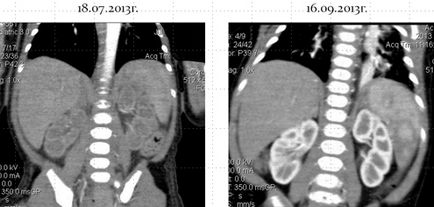

După 2 luni pe fondul tratamentului cu propranolol, structura educației sa schimbat, șuntul arterio-venos a dispărut între ramura arterei hepatice comune și cea inferioară a venei cava.

Caracter dinamic schimbare structurii neoplasmul sub forma reducerii diametrului vaselor de sânge și dispariția șunt arterio-venos, împotriva tratamentului conservator a ajutat confirma diagnosticul „congenital (infantil) ficat hemangiom.“

De asemenea, după dispariția șuntului arteriovenos, umplerea sângelui a organelor parenchimale sa îmbunătățit.